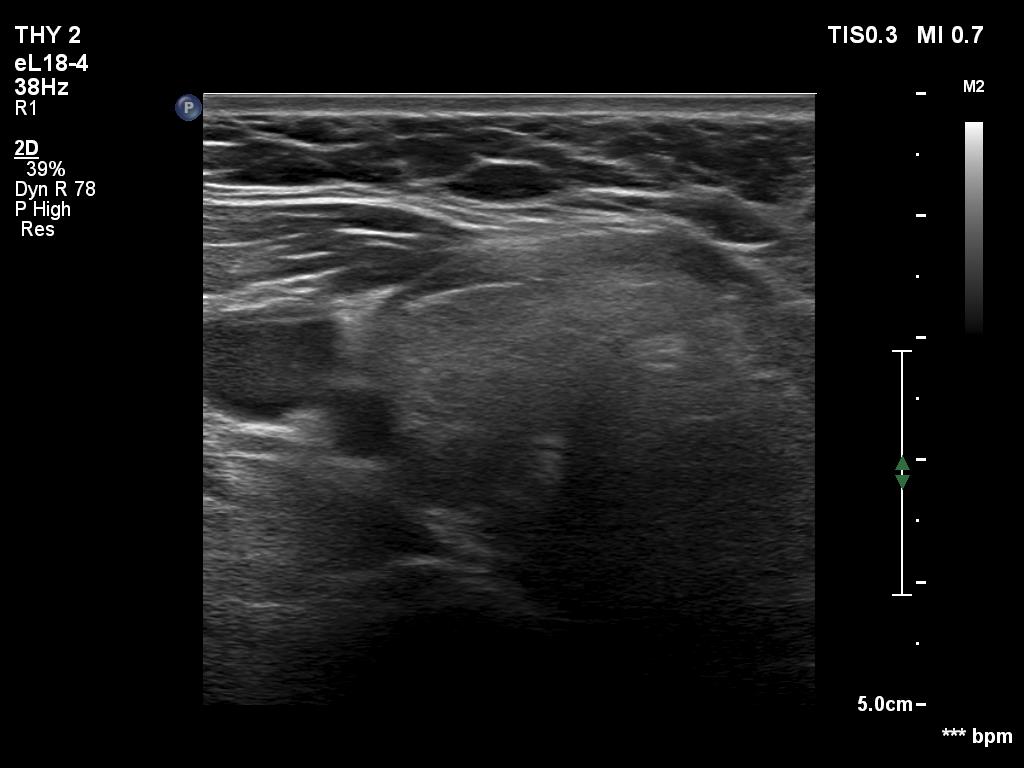

Ultrasonography. The thyroid was echonormal. Using higher frequency three discrete hypoechoic lesions were found, one in the middle dorsal part of the right lobe, one in the middle and a third one in the lower dorsal part of the left lobe. By decreasing the frequency, the presence of only the third one could be confirmed.

Comment. It is a rule that larger the distance from the probe worse the permeability of ultrasound wave. This can lead in certain patients (overweighted ones or frequently in men) that the dorsal part of the thyroid lobe can deceptively look darker, i.e. hypoechoic. If we have any doubt, by lowering the frequency i.e. increasing the penetrance, the real situation can be much better to judge.

This happened in this patient. If we would trust the pattern gained by higher frequency settings, we would falsely diagnose at least one additional nodule.